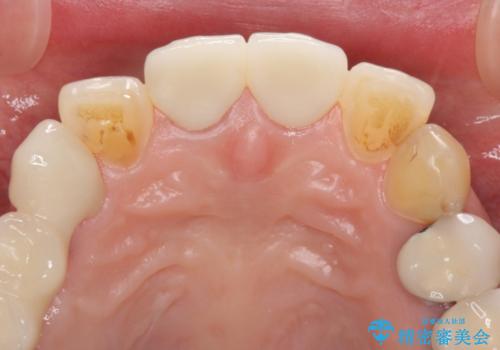

神経は残せていましたが、歯の色の変色が著しく、また広がった大きな形をしていたため、前歯2本をオールセラミッククラウンにて補綴することとしました。

前歯2本を同時に処置したことにより、色合いも形態もバランスの取れた仕上がりとすることができました。